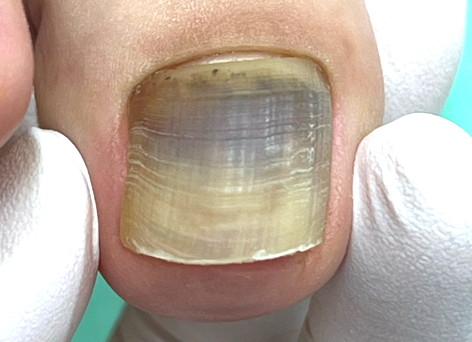

爪が分厚かったり変形している場合は、爪の機能が衰えてしまっている状態です。

原因は様々ですが一度機能が衰えてしまうと、時間が経っても元の正常な爪には残念ながら戻りません。